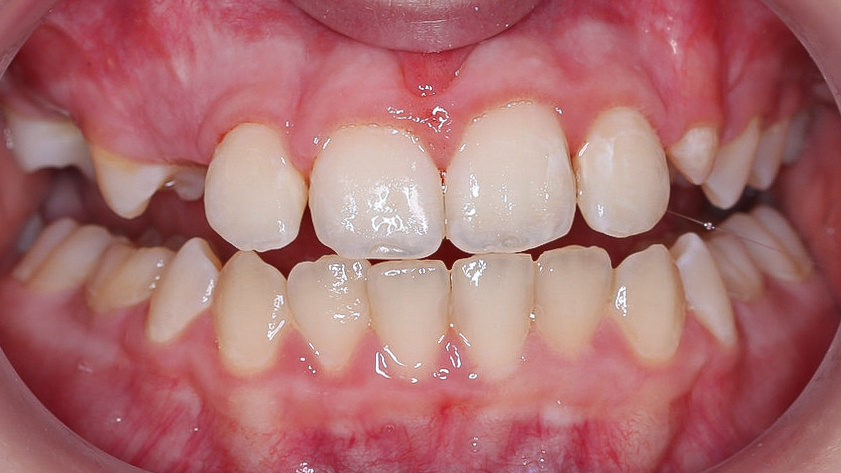

Результат лечения

Алина носила брекеты 10 месяцев. После снятия системы зубы на месте, прикус скорректирован, а нижняя челюсть заметно подросла. При этом ортодонтические аппараты на нижней челюсти не фиксировались, для ее роста просто появилось достаточно места👍

В случае Алины не понадобилась фиксация зубов проволочным ретейнером и ночные ретенционные каппы. Челюсть девочки находится в стадии активного роста, происходит движение корней клыков, прорезывание других постоянных зубов. Фиксация каппами и ретейнером может нарушить этот процесс.

Правильное положение передних зубов

На данном этапе у Алины сохраняется асимметрия десневого края, но эту проблему необходимо корректировать позже. По мере роста челюсти и прорезывания зубов она может скорректироваться даже без лечения.

После снятия брекет-системы Алина посещает ортодонта раз в полгода. На приемах следим за правильным прорезыванием постоянных зубов, контролируем рост нижней челюсти.